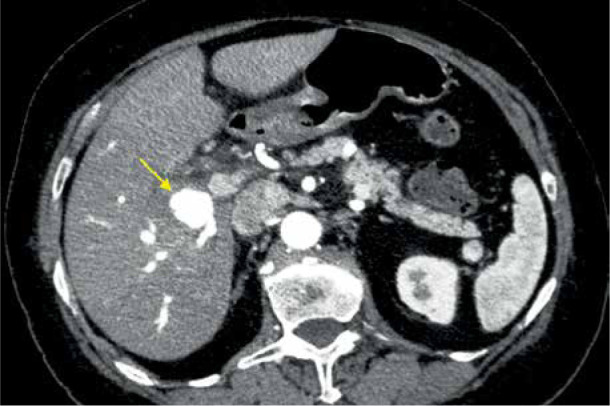

一名系统性红斑狼疮血管炎患者的右肝动脉分支肝内动脉瘤。

Intrahepatic aneurysm in a branch of the right hepatic artery in a patient with vasculitis due to systemic lupus erythematosus.